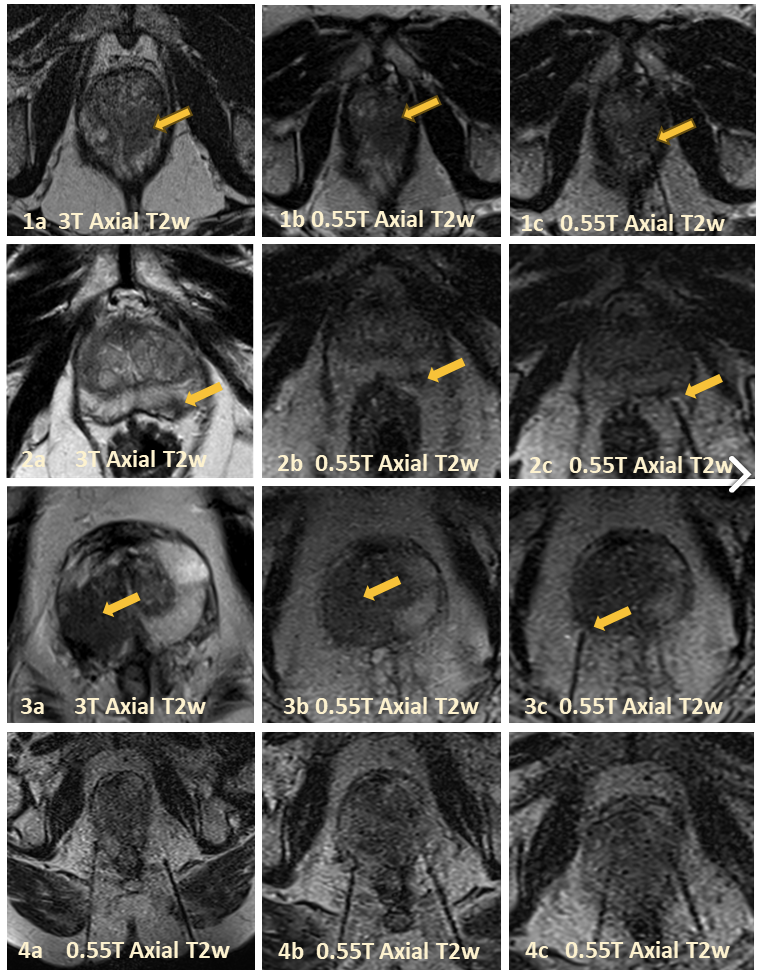

‘Rationale and Clinical Feasibility of MRI-Guided Percutaneous Transgluteal Route In-Bore Prostate Biopsy at 0.55T’ received Summa Cum Laude award in ISMRM 2025.